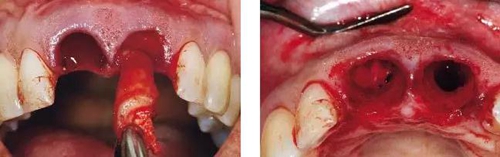

圖3、微創(chuàng)小心拔除雙側(cè)中切牙,保護(hù)牙齦緣和齦乳頭不受損傷。

圖4、觸診檢查感知頰側(cè)有骨缺損,且瘺管與牙槽窩內(nèi)肉芽組織相連。

圖5、左側(cè)用探針檢查可感知牙槽窩根方頰側(cè)軟硬組織的缺損??梢娧篱g乳頭很薄。

圖6、前庭溝半圓形切口,翻瓣后暴露左側(cè)和右側(cè)的骨缺損。